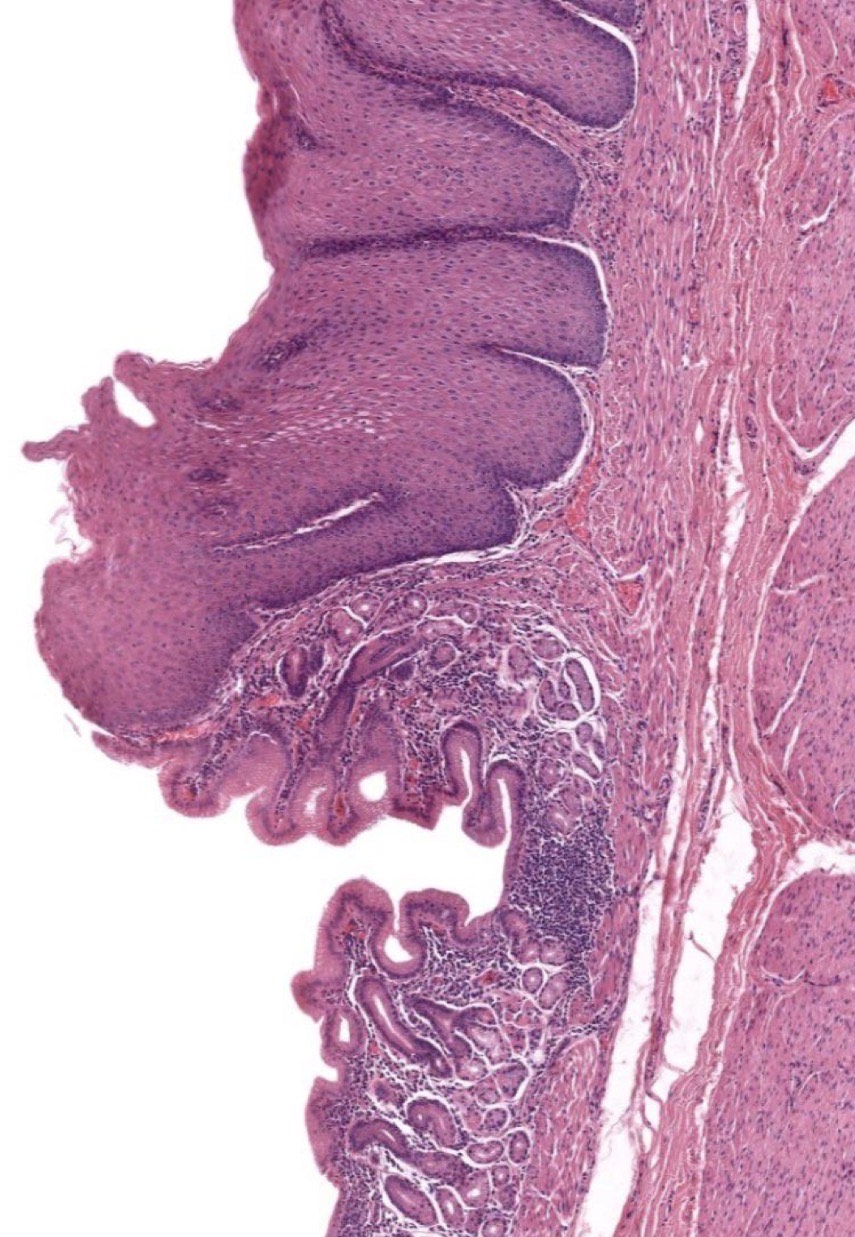

What is Gastroesophageal Junction?

Boundary btwn Esophagus & Stomach to prevent Reflux. Eso = Non-K strat squamous epit vs Stom = simple columnar epit and has G

Identify the Structure

Gastroesophageal Junction. Top is Eso bottom is Stomach (cardiac)

Gastroesophageal Junction. Left is Eso Right is Stomach (cardiac)